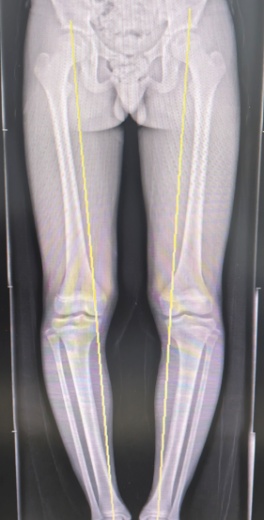

患者站立位力线

医生发现检查和评估后发现:小李的O型腿导致双下肢受力线严重偏移,走路、跑跳时的重量几乎全部压在膝盖内侧,长期的超负荷压力,不仅磨坏了关节内的半月板,还引发了一系列结构改变和疼痛症状。